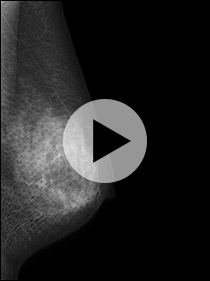

Q. 3Dマンモグラフィー(トモシンセシス撮影)と2Dマンモグラフィーの見え方はどう違うのですか?

A. 角度を変えて複数の方向から撮影されるため、従来の撮影よりも症状が判別しやすくなっています。

2D画像サンプル

3D画像サンプル